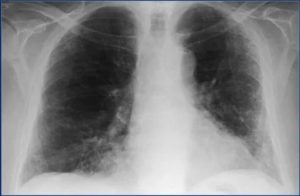

Самым распространенным методом диагностики легких является – флюорография. Но если врач подозревает, что у пациента есть спайки, то больной отправляется на рентген. По рентгеновскому снимку распознать синехию можно по мутным темным пятнам. Она выглядит, как теневое затемнение и неподвижна при вдохе и выдохе.

Иногда выявляется деформация грудной клетки и диафрагмы. Чаще всего спаечный процесс отмечается в нижней части легкого. Такой вид спаек – плевродиафрагмальный, а вид спаек в верхней части – плевроапикальный.